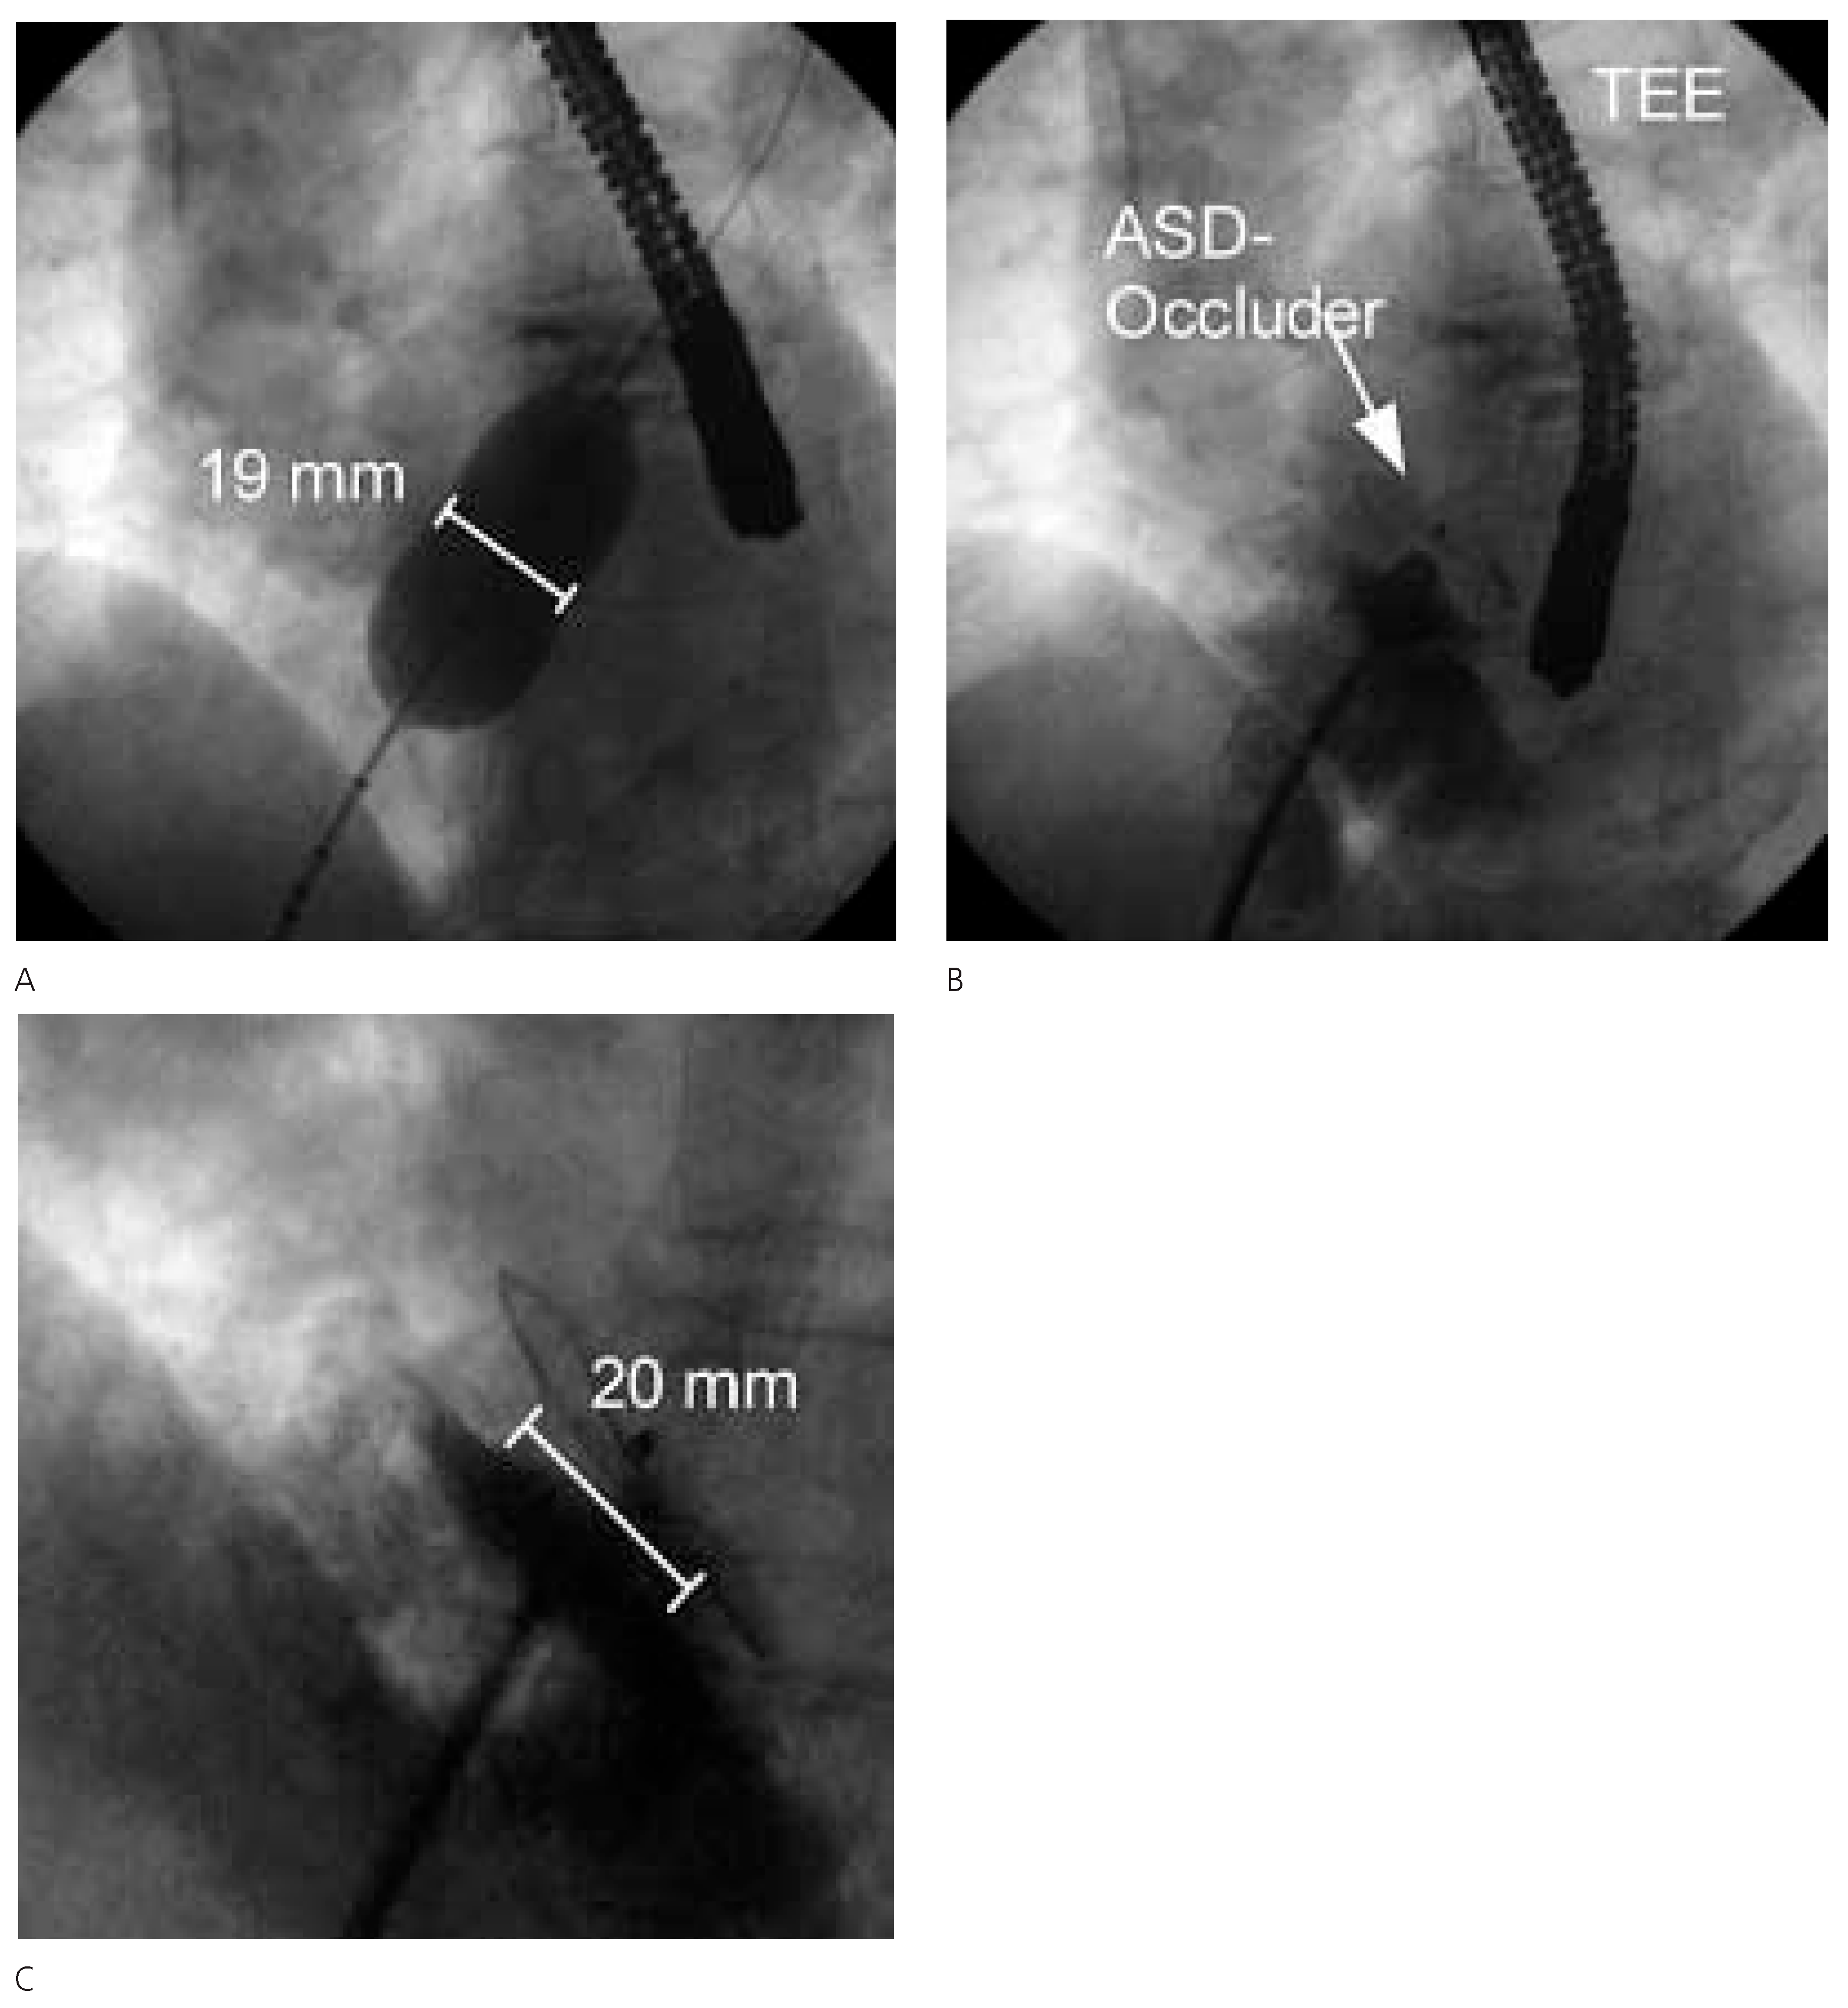

Figure 3.

TEE vor (A) und nach (B) Verschluss mit Amplatzer-Occluder 20 mm. Zu beachten die Position des ASD nahe der Aortenwurzel.